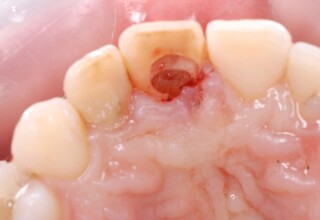

Δύσχρωμα απονευρωμένα δόντια

Μια ιδιαίτερη περίπτωση δύσχρωμων απονευρωμένων δοντιών που ο κεντρικός είχε βλάβη από εξωτερική απορρόφηση. Έγινε καθαρισμός του κεντρικού από την βλάβη και επειδή δεν μπορούσε να λευκανθεί λόγω της επαφής με τα ούλα, σφραγίστηκε σε πρώτη φάση, μετά λευκάνθηκε και στο τέλος έγινε η τελική αποκατάσταση.

Αρχική εμφάνιση

Τελική εμφάνιση